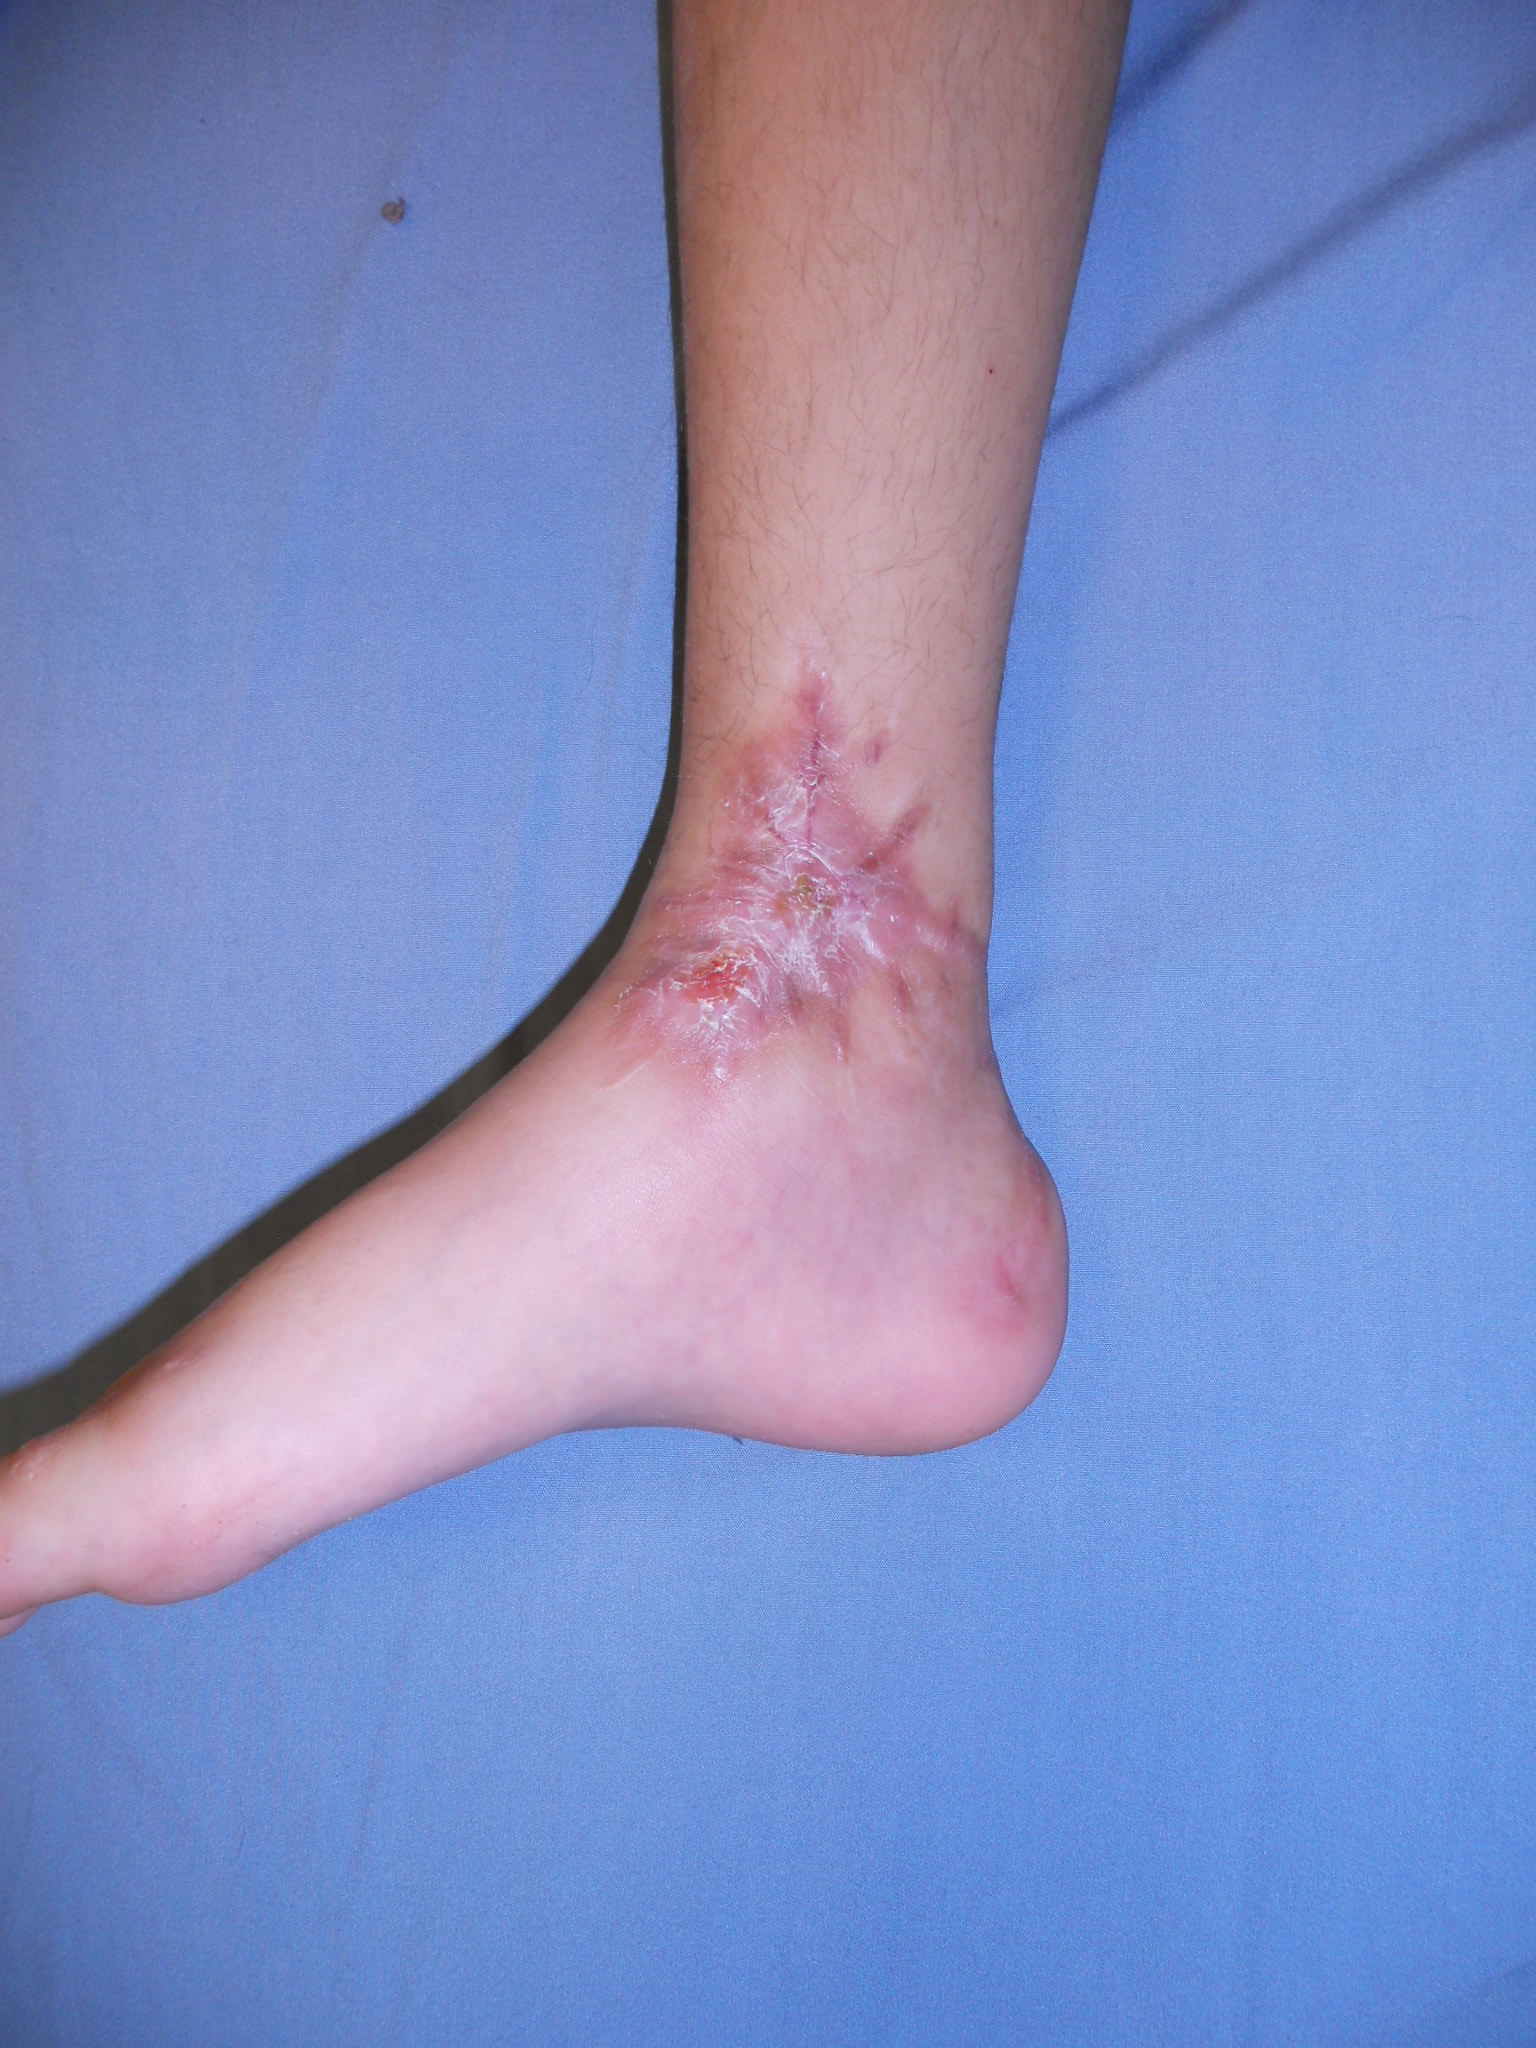

IntroducciónLas fracturas Salter-Harris VI (SHVI) son lesiones que se caracterizan por presentar ablación del anillo pericondral. Son infrecuentes en niños pero potencialmente devastadoras. El objetivo de este estudio fue evaluar el mecanismo de producción, el tratamiento y los resultados funcionales de estas lesiones localizadas en el pie y el tobillo.Material y métodosSe analizaron retrospectivamente todos los pacientes con lesiones SHVI de tobillo y pie tratadas entre Enero de 2010 y Enero de 2013. Se documentaron datos demográficos, clasificación, mecanismo de lesión, tipo de lesiones asociadas y número de cirugías que requirieron. Los pacientes fueron evaluados funcionalmente con el score de AOFAS y radiográficamente para determinar la viabilidad de la fisis, acortamiento del miembro o deformidad angular.ResultadosSe analizaron 5 fracturas en 4 pacientes (3 masculinos y 1 femenino). La edad promedio al momento de la lesión fue de 7.5 años (rango, 6 a 10 años). El seguimiento promedio fue de 26.2 meses (rango, 12 - 37 meses). De acuerdo a la subclasificación de Peterson 3 pertenecían al grupo A, 1 al B y 1 al C. 3 lesiones se produjeron como consecuencia de accidentes de moto y 2 por auto versus peatón. Todos los casos se acompañaron de pérdida de sustancia, el 75% presentaba lesiones en más de un hueso y el 50% lesiones tendinosas asociadas. Cada paciente requirió un promedio de 3.2 cirugías (rango, 2 a 5). El score AOFAS promedio fue de 79.8 puntos (rango, 62 – 100 puntos). Radiográficamente, solo el 40% de las fisis afectadas permanecían viables al último control.ConclusiónLas fracturas SHVI se acompañan de una gran variedad de lesiones asociadas, requieren múltiples cirugías y suelen producir un cierre precoz de la fisis y algún grado de discapacidad. Se requieren medidas de prevención para evitar la exposición de los niños a este tipo de lesiones. El tratamiento temprano es fundamental para prevenir el desarrollo de deformidades.Descargas